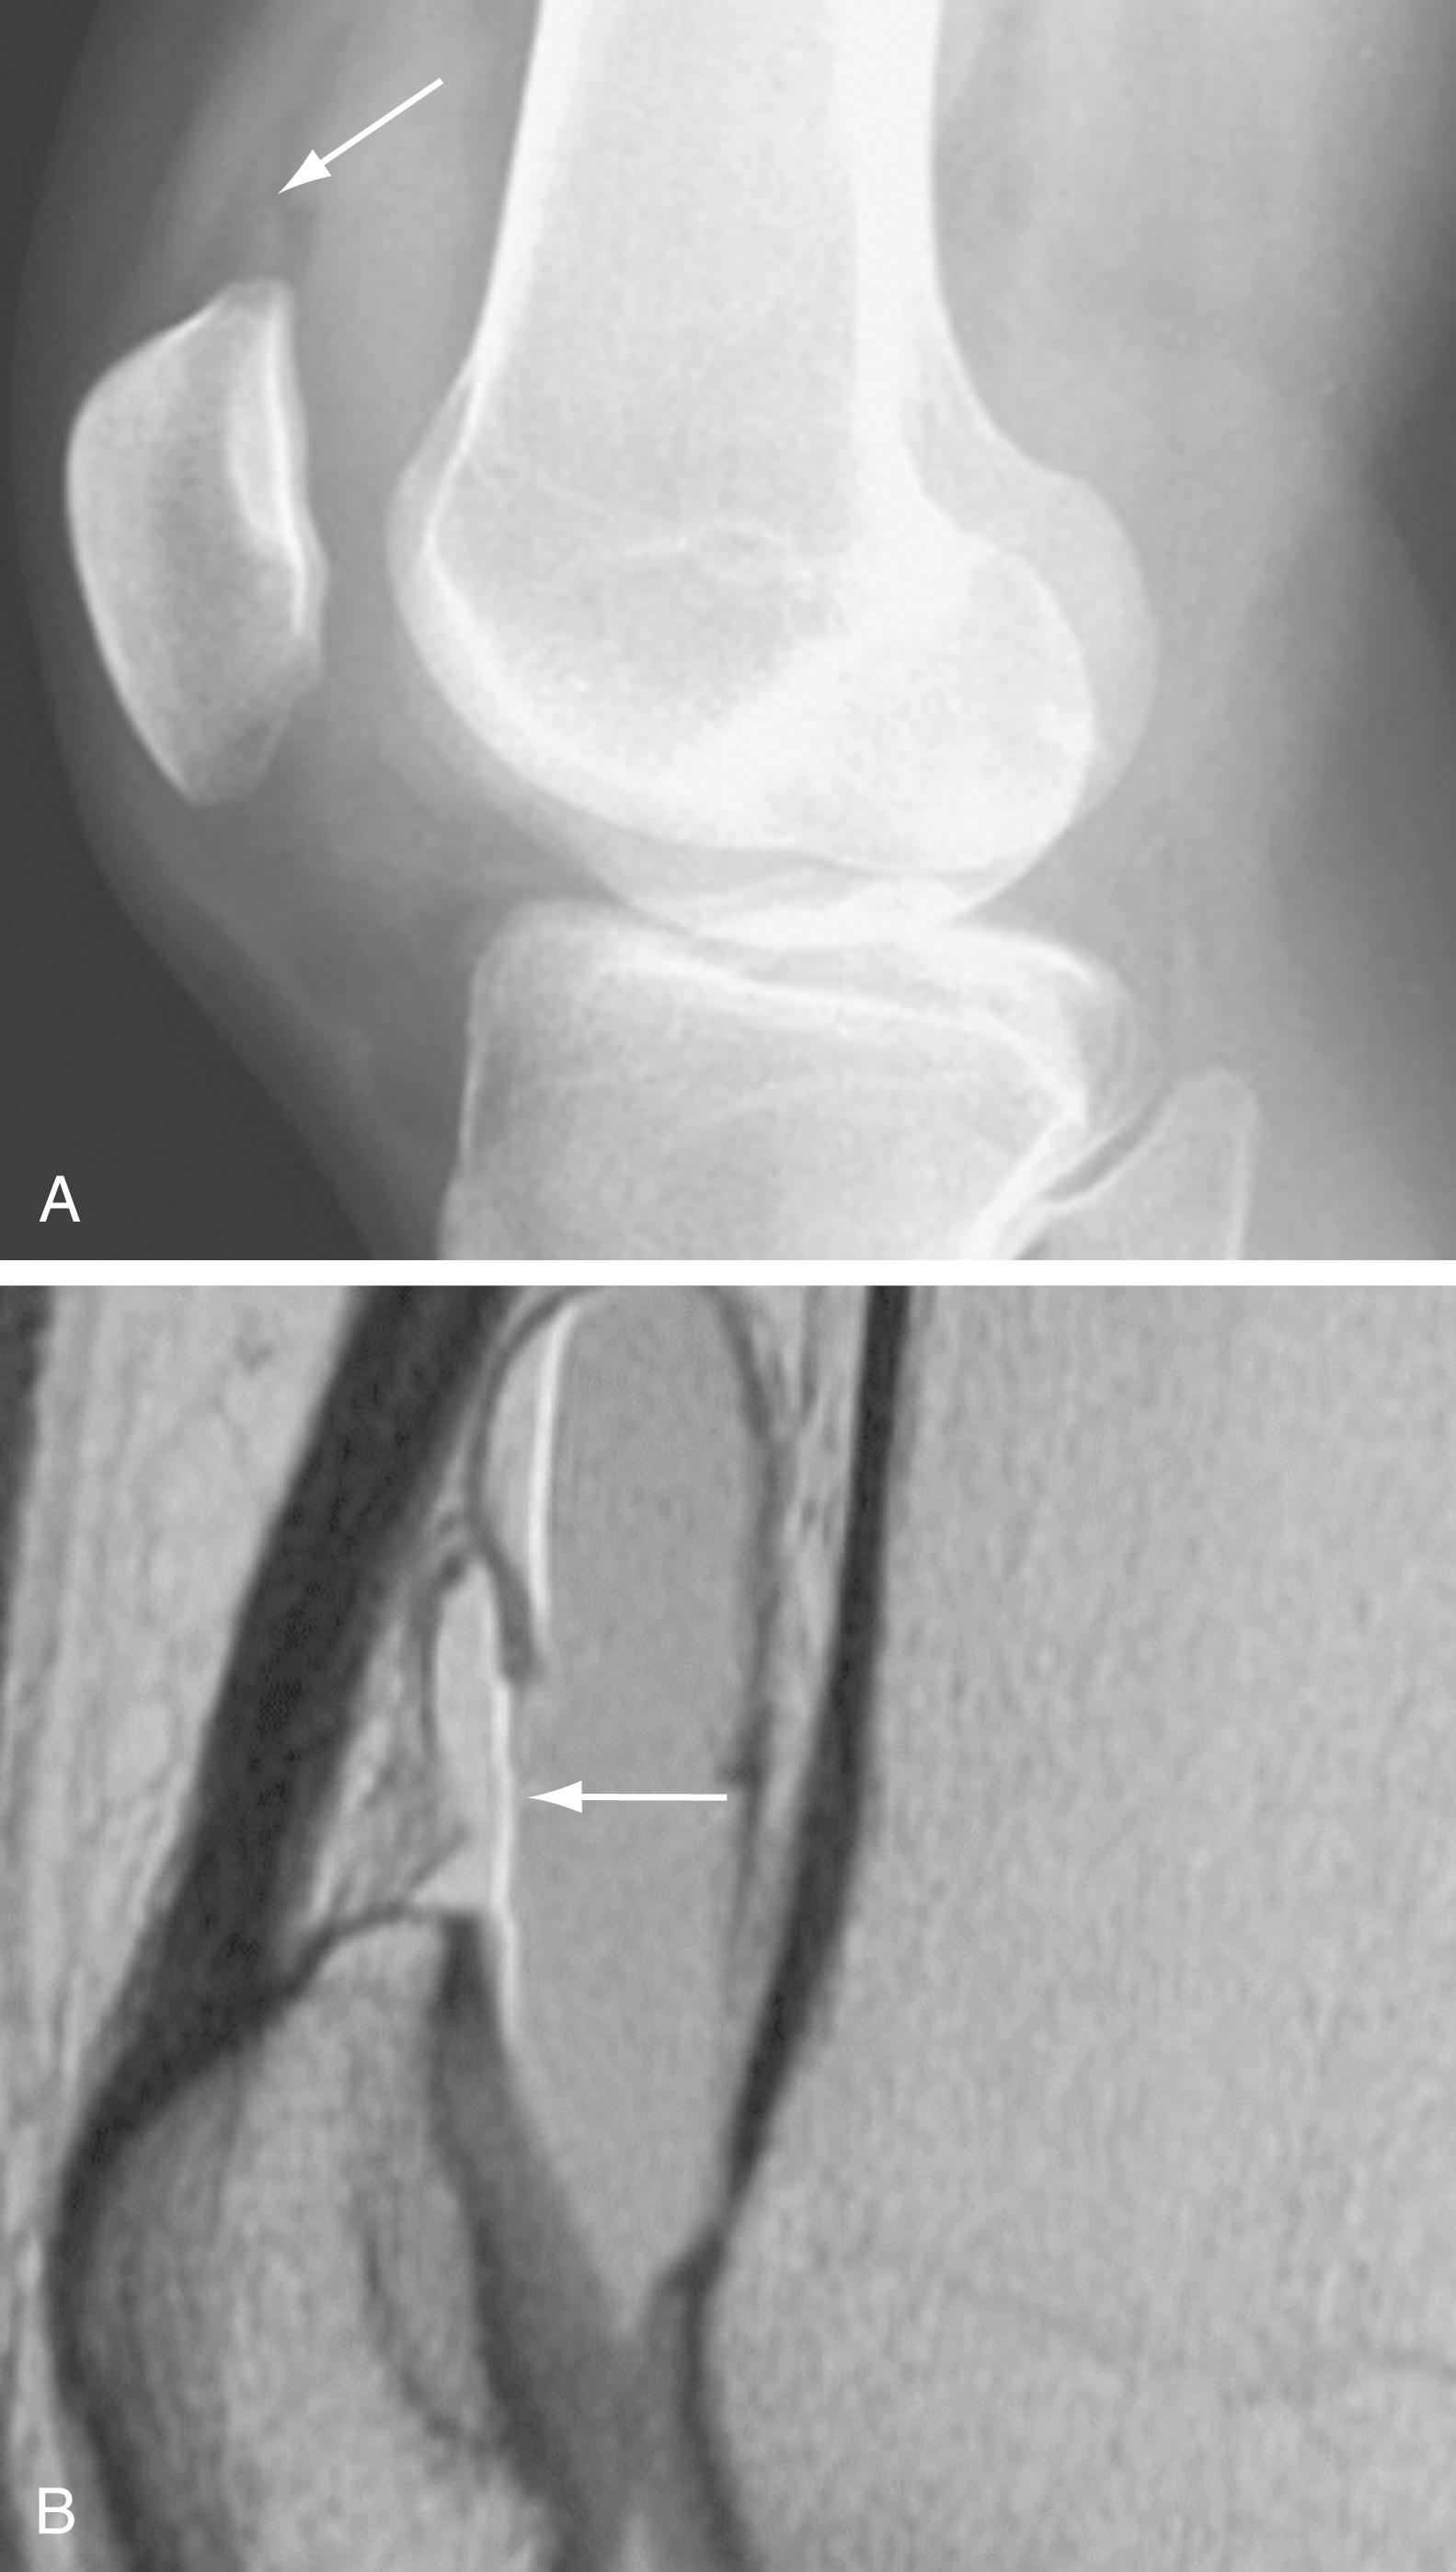

The Segond fracture represents a bone avulsion of the lateral tibial plateau ( Fig. 48.6 ). The avulsion occurs at the site of attachment of the lateral capsular ligament. On radiographs, an oval-shaped fragment can be seen adjacent to the lateral tibial plateau. Segond fractures are usually accompanied by ACL disruption. Most Segond fractures are caused by sports injuries; the mechanism is almost always knee flexion with excessive internal rotation and varus stress.

Fig. 48.6, Segond Fracture.